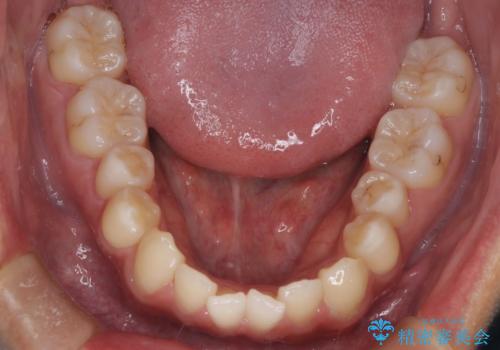

【MSE+インビザライン】前歯のガタガタ

- 前歯の凸凹を主訴に来院されました。

上の歯のアーチが狭窄していたため、骨の幅を広くするためにMSE(急速拡大装置)を使用してからインビザライン にて治療を行いました。

MSE(急速拡大装置)を用いたことで、短期間で奥歯の噛み合わせもしっかりと治すことができました。